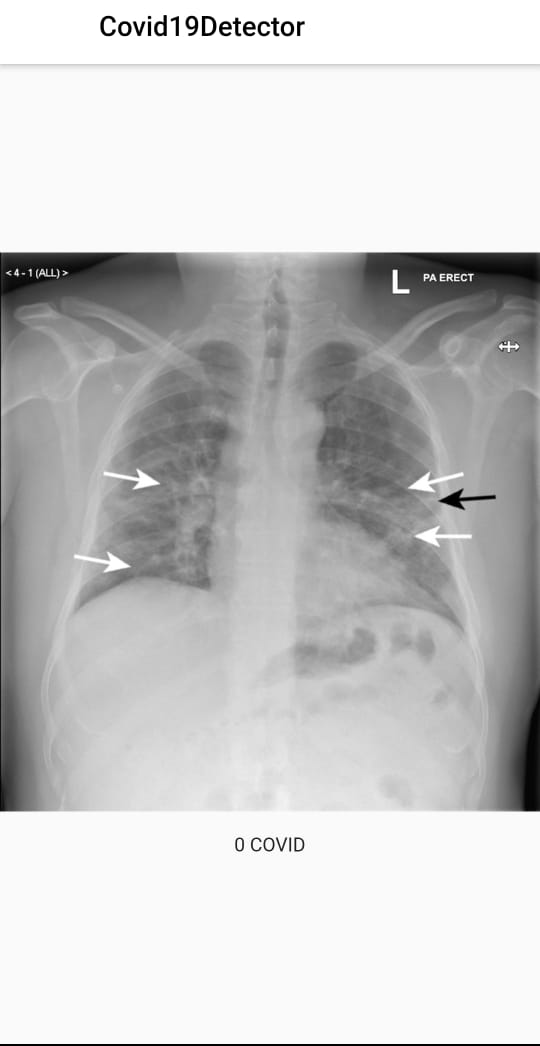

1. Covid detection through lung x-ray using a Kaggle dataset and embedding in the flutter app through Tensorflow.